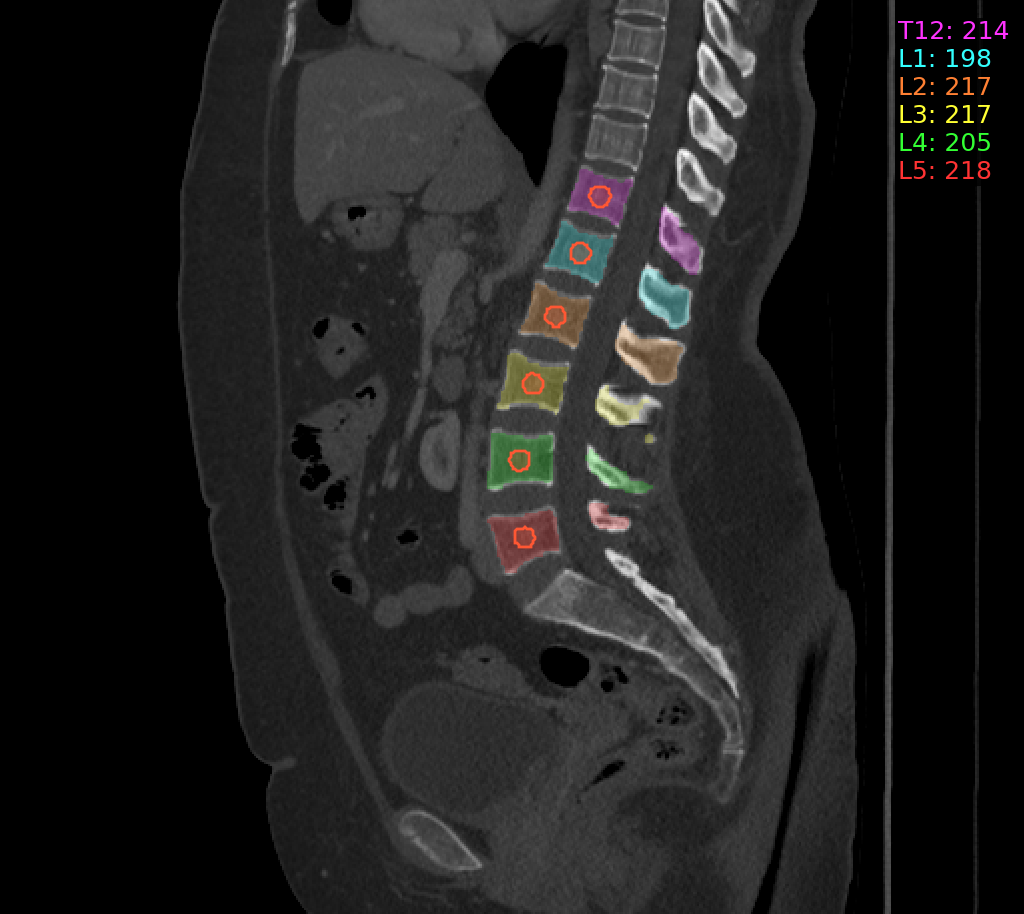

## Spine Bone Mineral Density from 3D Trabecular Bone Regions at T12-L5

### Usage

```bash

bin/C2C spine -i

```

- input_path should contain a DICOM series or subfolders that contain DICOM series.

### Example Output Image